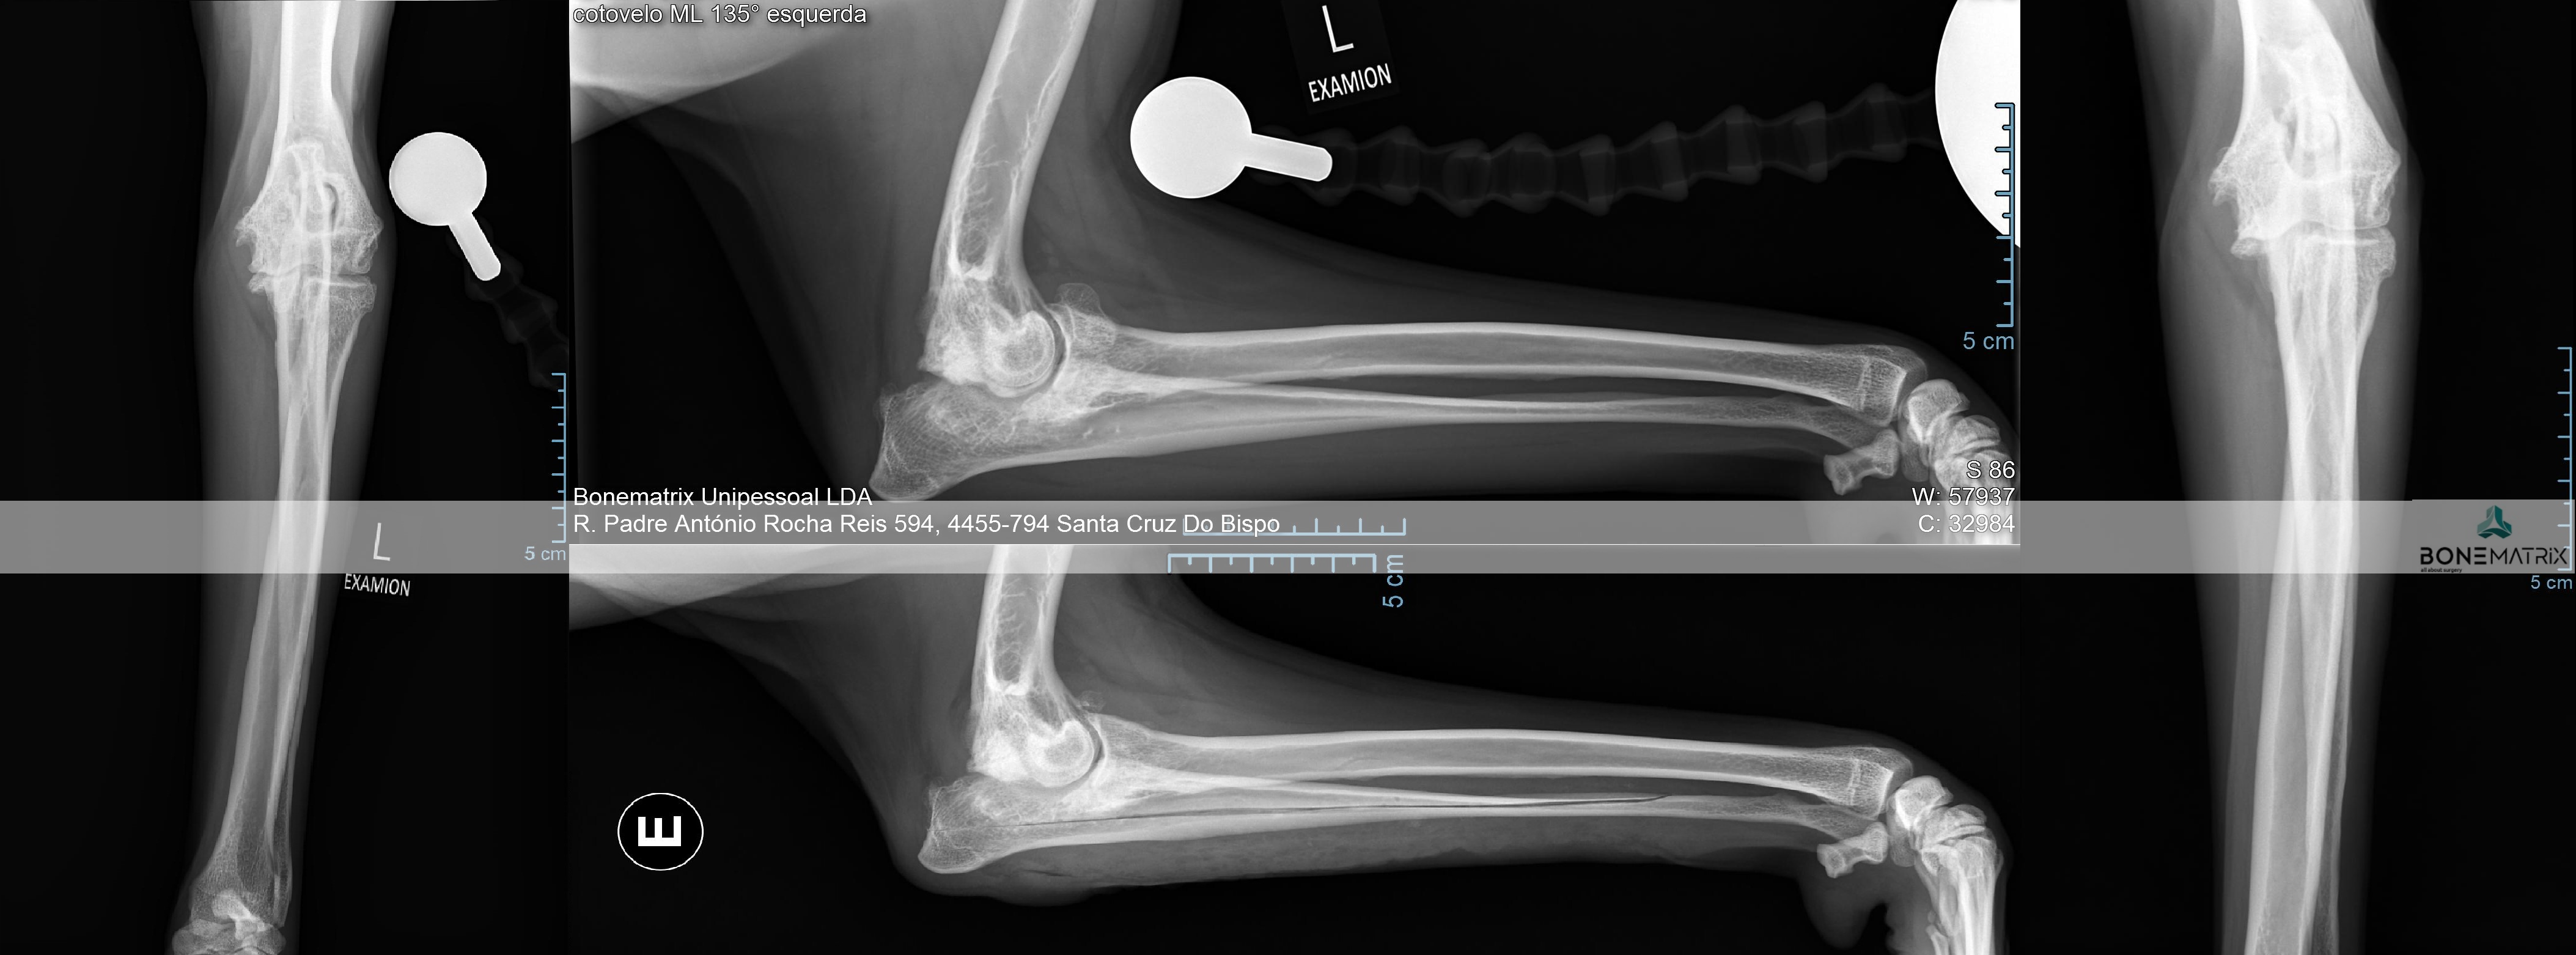

A displasia de cotovelo é uma doença de desenvolvimento caracterizada pela incongruência do cotovelo.

Dada a componente genética, frequentemente envolvida no decorrer deste processo, a patologia apresenta-se por norma bilateralmente, podendo assumir gravidade diferente em ambos os cotovelos.

Esta patologia quando unilateral, por norma, está relacionada com um evento traumático, ocorrido durante o crescimento do animal.

Quais as consequências desta patologia a nível articular?

A displasia de cotovelo pode assumir várias apresentações, entre elas, a não união do processo ancóneo, a fragmentação do processo coronóide, a osteocondrite dissecante, doença do compartimento medial e a incongruência per si.

Todas estas apresentações tem em comum contribuírem para o desenvolvimento acelerado de um quadro de osteoartrite a nível intra-articular.

Como é criada esta incongruência?

A articulação do cotovelo é constituída por 3 ossos, o rádio, a ulna e o úmero.

A incongruência do rádio resulta na apresentação deste osso mais curto que a ulna. Isto resulta num excesso de pressão sobre regiões da ulna - resulta com frequência na fragmentação do processo coronóide.

Quando a apresentação contrária ocorre, ou seja, o rádio apresenta-se mais elevado que a ulna, é exercida demasiada pressão sobre o processo ancóneo - resultando com frequência na não união do processo ancóneo.

Quando a incongruência envolve o úmero outras lesões podem ser desenvolvidas que envolvem o desalinhamento articular entre o úmero e a ulna.

As incongruências descritas também podem ser consequência de um encerramento precoce traumático das placas de crescimento destes ossos (locais responsáveis pelo crescimento longitudinal dos ossos).

Predisposição

Os cães com predisposição para a apresentação desta patologia são os cães de crescimento rápido, ou seja, cães de raça grande a gigante, onde existe com frequência problemas no crescimento harmonioso destes ossos.

Como diagnosticar/ Sinais?

A apresentação desta patologia em fases iniciais apresenta, com frequência, sinais subtis, daí a necessidade de realização de despiste de displasia de anca durante o crescimento do animal (idealmente 5 meses) para que a doença possa ser detetada antes que ocorra um desenvolvimento significativo de lesões de osteoartrite a nível intra-articular.

O diagnóstico pode ser realizado por meio de estudo radiográfico.

Contudo são indicadas técnicas de imagem avançada (tomografia axial computorizada) ou artroscopia para a realização do diagnóstico final e definição de abordagem terapêutica.

Qual o tratamento indicado?

O tratamento depende da forma de apresentação da doença a nível articular.

Vários são os procedimentos terapêuticos que podem ser feitos com recurso a artroscopia, nomeadamente desbridamento de lesões cartilagíneas, remoção de fragmentos do processo coronóide, remoção sub-total do processo coronóide, assim como também é possível a remoção de flaps de lesões de osteocondrite dissecante.

A resolução da incongruência articular é realizada por meio de um corte corretivo realizada na ulna. Este corte vai permitir que este osso se readapte à articulação de forma a que todas as estruturas constituintes da articulação suportem o peso de uma forma equilibrada, sem sobrecarregar nenhuma região. A cirurgia realizada com maior frequência neste sentido designa-se por PLUS.